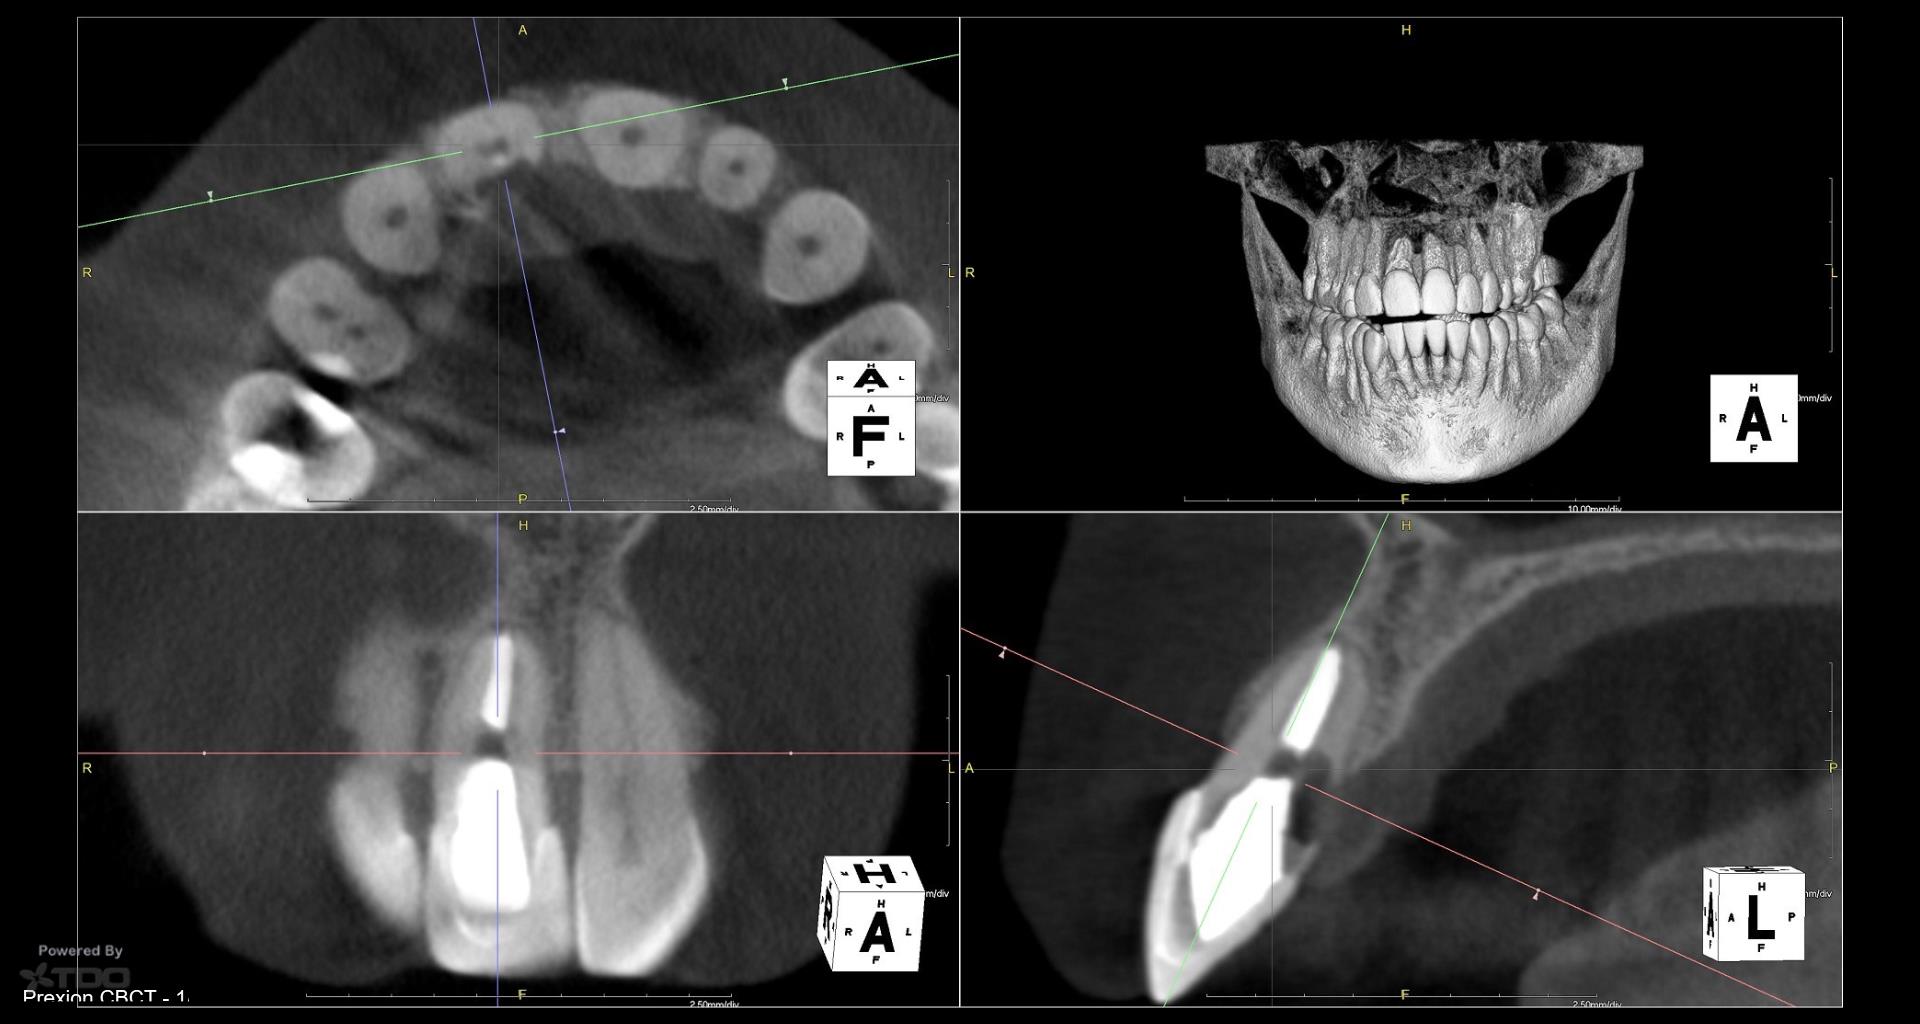

What is the treatment option being considered? Can you flap and repair? The lesion appears well-demarcated, without bone ingrowth, so it may be a simple repair with minimal ostectomy. If the patient can tolerate a couple black triangles (despite only flapping the palatal), then I might do it.